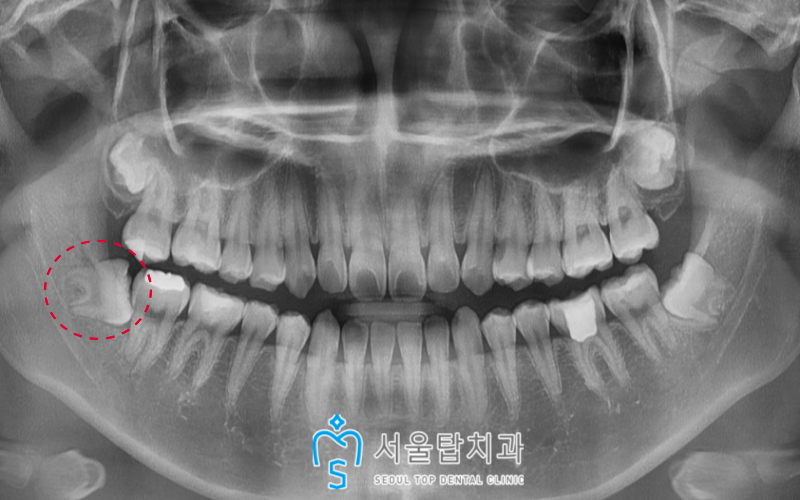

파노라마 사진상에서도

남은 뿌리 없이 깔끔하게

발치가 된 모습을 확인할 수 있습니다. ^^